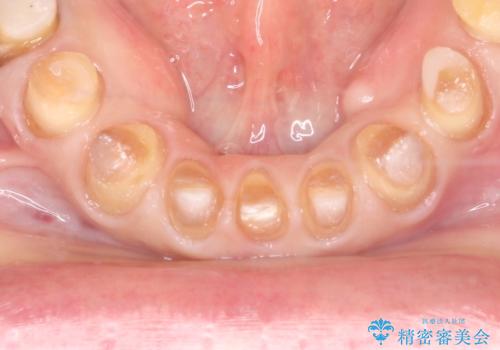

- 昔、他院で治療したダイレクトボンディング(歯の表面にだけ白い材料を盛る治療)のやりかえを主訴に来院されました。叢生の改善も同時に行うためにオールセラミッククラウンにより治療を行いました。

ダイレクトボンディングでの治療より、天然歯に近い見た目を再現することができます。